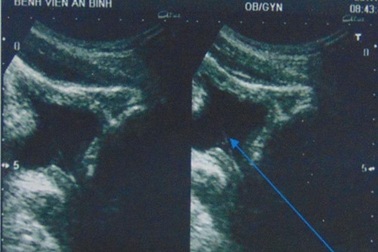

Tự lấy sỏi thận qua đường niệu bằng… cọng cỏBệnh viện An Bình (TP.HCM) vừa ghi nhận một trường hợp hi hữu, bệnh nhân tự lấy dị vật nghi sỏi thận qua đường niệu bằng... cọng cỏ.